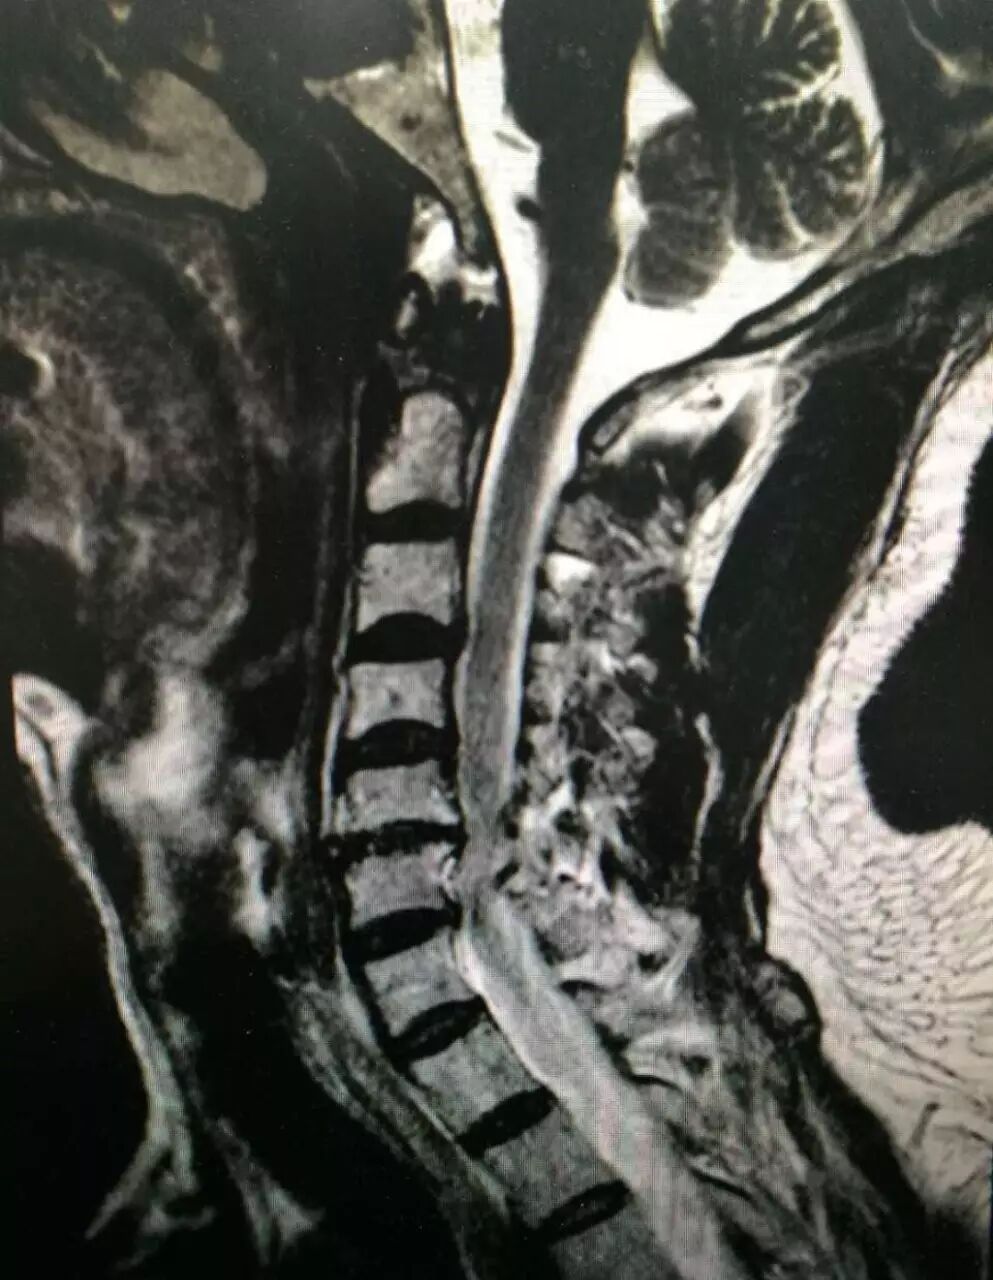

核磁共振机使用较强大的磁场,使人体中所有水分子磁场的磁力线方向一致,这时磁共振机的磁场突然消失,身体中水分子的磁力线方向,突然恢复到原来随意排列的状态。简单说就相当于用手摇一摇,让水分子振动起来,再平静下来,感受一下里面的振动。所以,核磁共振(MRI)也被戏说为是摇摇看的检查

颈椎病、腰椎间盘突出等椎间盘疾病需要观察椎间盘与相应的神经根,要想更好观察这些软组织,最优选择就是核磁。同样,对于关节、肌肉、脂肪组织检查,核磁也是首选。